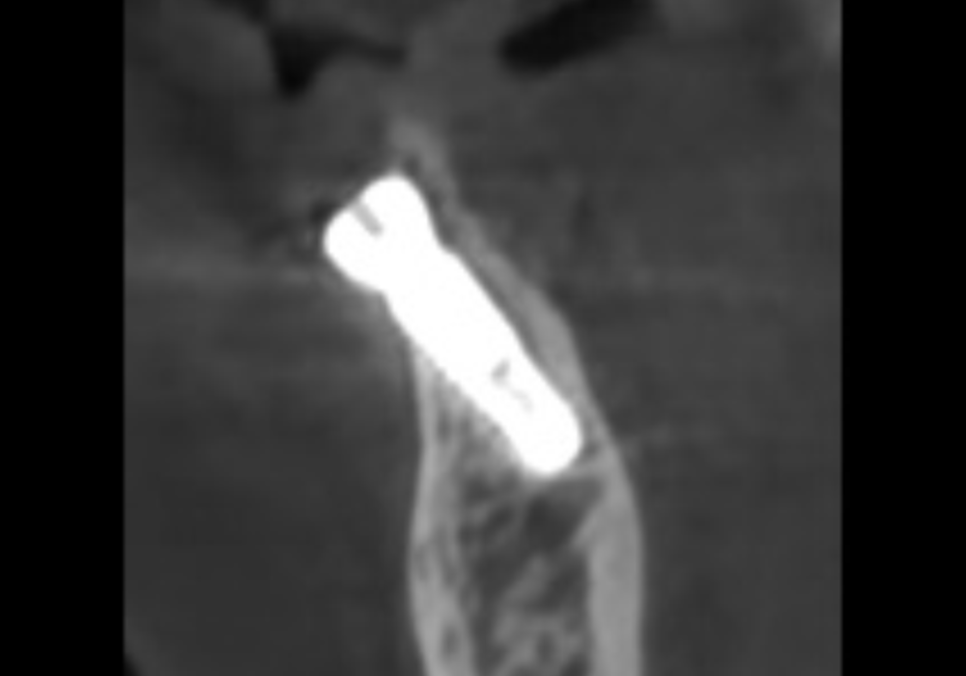

이 환자분은 과거에 아래

중앙 앞니(#31, 41)가 흔들리기 시작했을 때,

발치가 두려워 철사로

양옆 치아까지 넓게 묶어두셨다고 해요~

251022

당장 흔들림이 없으니

안심하고 오랜 시간을 보내셨지만,

정작 뿌리 끝에 박힌 염증 원인은

그대로 남아 있었죠.

결국 중앙 앞니에서 시작된 염증은

조용히 옆 치아(#32, 42)까지 퍼져나갔습니다.

내원 당시에는

이미 철사로도 감당할 수 없을 만큼

4개의 치아가 한꺼번에

심하게 흔들리고 있었고,

251028

주변 잇몸뼈가 광범위하게 녹아내려

결국, 앞니 4개를 모두 발치하고

임플란트를 진행했습니다.